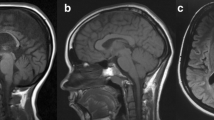

França MC, D’Abreu A, Maurer-Morelli CV, Seccolin R, Appenzeller S, Alessio A, et al. Prospective neuroimaging study in hereditary spastic paraplegia with thin corpus callosum. Mov Disord. 2007;22:1556–62.